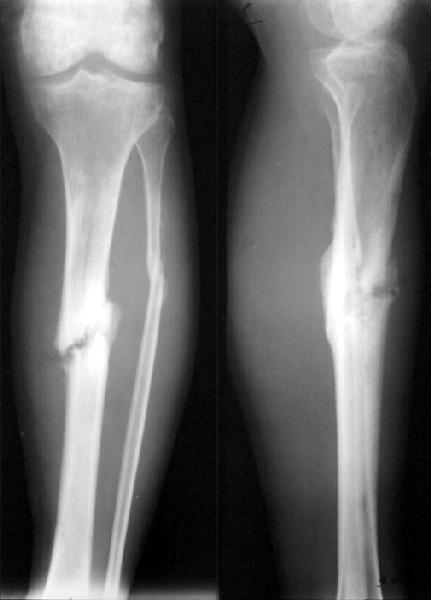

Пациент 26 лет 7.02.2002 был сбит легковой машиной в небольшом городке. По поводу перелома костей голени 15.02.02 в местной больнице был наложен аппарат, который был снят 25.05.02. Перелом закрытый, воспаления таней у спиц, со слов больного, не было. После снятия была патологическая полдвижность, наложена гипсовая шина, которую пациент через месяц снял сам. Ходил с частичной нагрузкой. Сейчас ходит с тростью, отмечает болезненность в проекции перелома. Явной патологической подвижности при осмотре не выявили, хотя, конечно, нагрузки прикладывали не самые максимальные. Снимки свежие (фас+профиль и косые).Какой здесь на сегодня уместен диагноз? Псевдартроз? Несросшийся перелом? Замедленная консолидация? Сросшийся на органиченном участке?Как-то иначе? В плане у нас - закрыто заштифтовать большеберцовую кость "как есть" с динамическим блокированием. Или потребуется закрытая остеоклазия? Надо ли делать остеотомию малоберцовой? Нужны ли, на Ваш взгляд, еще какие-то дополнительные меры, костная пластика, например?Заранее спасибо.

It is a hypertropic non union. IT NEEDS REAMINGG OF THE TIBIA WITH LARGEST REAMEAR AND PUT A LARGEST NAIL NO.11 OR 12 IF AVAILABLE. OSTOTOMY

WITH SOME SHORTENIG OF FIBULA. DYNAMIC LOCKING

Из вариантов "подчеркну" Псевдоартроз. Тугой (по Г.Я.Эпштейну). Возможно, А.В.Русаков сказал бы, что имеет место "Синдесмоз", а Н.С.Косинская

поставила диагноз "Фиброзный ложный сустав" или "Фиброзное сращение".

Думаю, это неср. перелом в стадии формирования псевдоартроза. На мой взгляд, нет надехды на спонтанное сростание и необходима хирургия.

This is a hypertrophic nonunion, fibulectomy + closed IM nailing should be enough.

It is a hypertrhic Nu - that means lack of stability. If there is no infection a reamed interlocking nailing is the procedure of choice. Fibualr ostetomy is a must- no qusteons- otherwise the tibial bone ends will not impact.

in Germany we call this "pseudarthrosis" , the difinition is that the fracture healing is delayed six months or more.

Regarding case of 26 yo patient with tibia shaft fracture that has gross motion 8 months after XF and casting.

Diagnosis? IMHO this is a delayed union with impending nonunion.